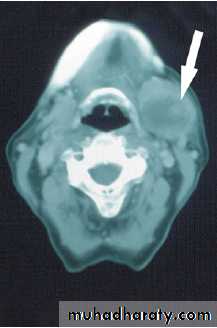

CT and MRI scanning

Fine-needle aspiration biopsy

(open surgical biopsy is contraindicated )

(no enucleation even if a benign lesion is suspected)